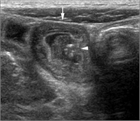

1. IgA血管炎は、免疫学的反応に起因する全身性の小型血管炎である。

1. 皮膚、関節、消化管、腎を主座とする多臓器病変を呈し、発症には感染症や薬剤を含む環境要因に加え、遺伝的要因の関与が示唆されている。